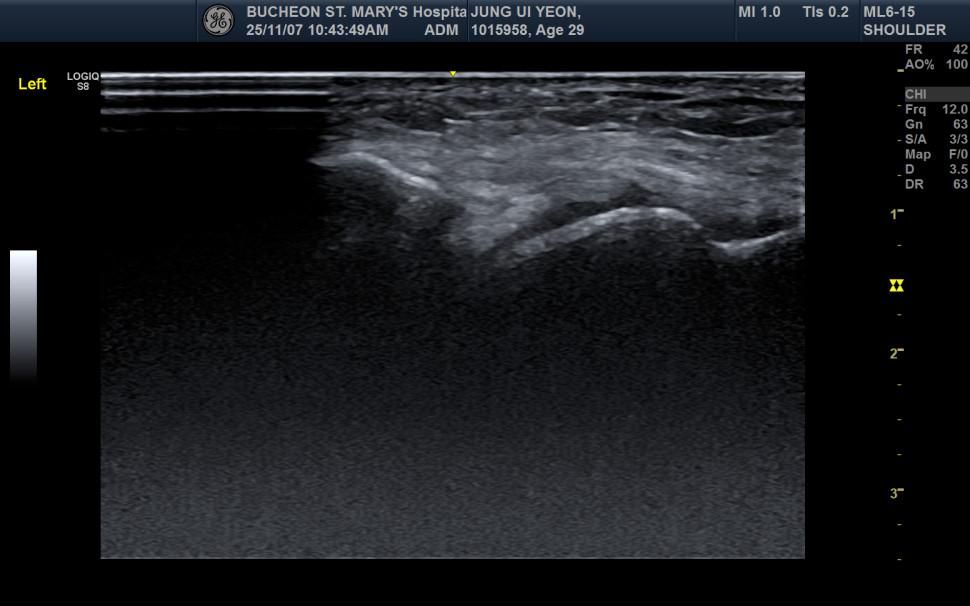

• 1번 째 사진

초음파 이미지를 기준으로 전체적인 구조 설명을 드리겠습니다. 다만 초음파 검사 특성상 프로프 잡은 의사의 주관이 개입되는 면이 있어 설명이 조금 부족하게 느껴지실 수 있습니다.

1. 초음파에서 발목 인대(특히 전거비인대 ATFL)가 보이는 위치: 발목 초음파의 전형적 구조는 다음과 같이 보입니다.

A. 위쪽 밝고 하얀 층

→ 피부, 피하조직입니다.

B. 그 아래 비교적 균일하게 보이는 밝은 띠 모양 구조

→ 인대(ligament)가 보이는 위치입니다. ATFL(전거비인대)은 초음파에서 얇고 밝게 보이는 섬유성 띠처럼 나타납니다.

3. 더 아래 어둡고 균질한 부분 → 근육 또는 지방 조직입니다

4. 가장 깊은 부분의 밝은 선 → 뼈 표면입니다. 뼈는 초음파에서 강하게 ‘하얗게’ 반사됩니다.

현재 올리신 이미지에서도 표면에서 조금 아래, 뼈 위를 가로지르는 밝은 섬유성 띠가 인대가 위치하는 구간입니다.